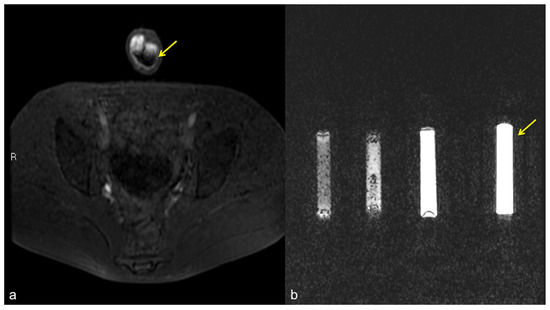

Figure 11.

Pseudo-stratification effect of the contrast agent. Cav-RM GRET1W 3D fat sat axial sequence after intra-cavernous administration of contrast agent (a): pseudo-layering artifact of the contrast agent in the cavernous bodies (arrow). Saline dilution of the contrast agent in a test tube (b): from the left side of the figure, note the progressive optimization of the contrast agent signal from 5 cc, 3 cc, 2 cc, to the optimal ratio of 1 cc of contrast agent in a total volume of 20 cc of solution (contrast agent + saline) (arrow).